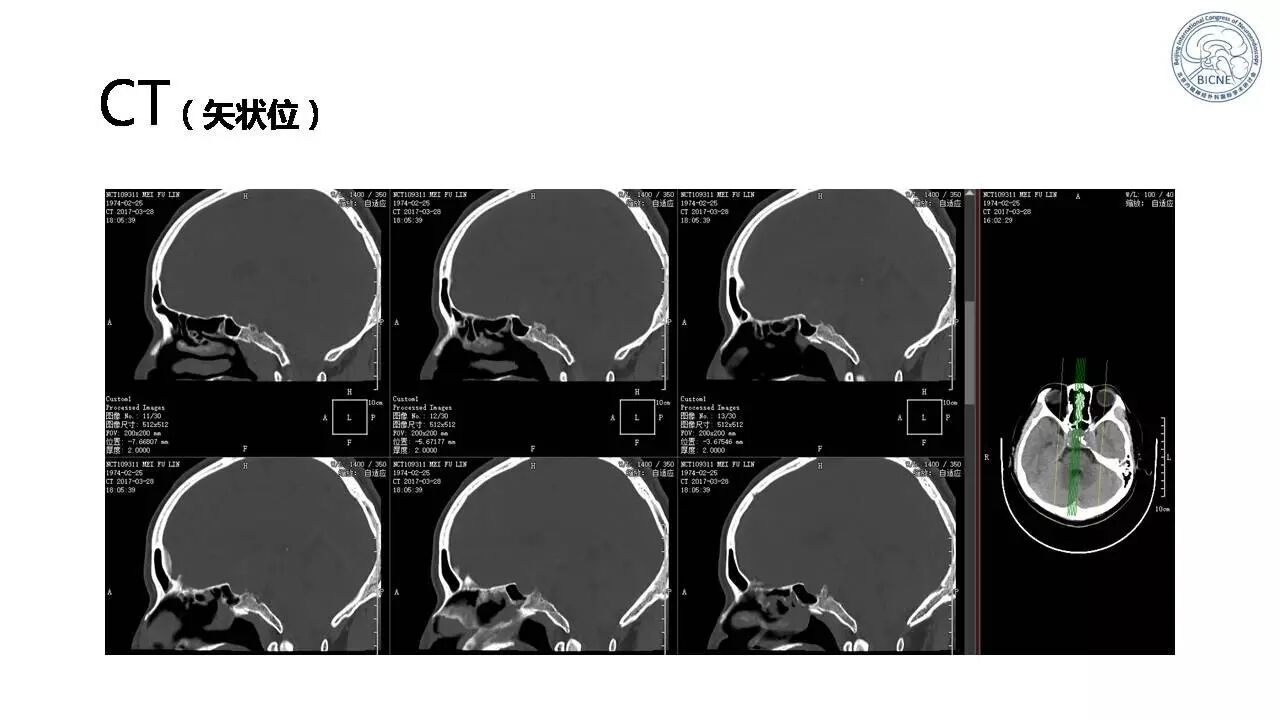

(四)张亚卓教授:复发脊索瘤经鼻内镜治疗

![]()